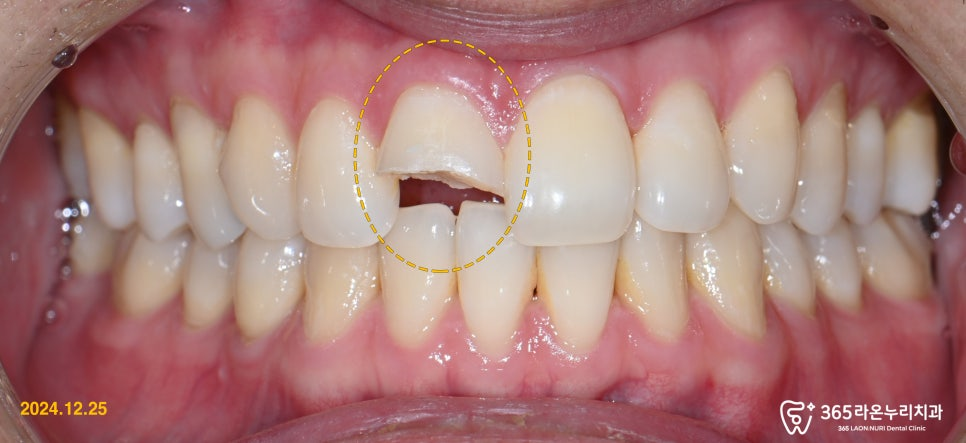

오늘은 앞니 파절로 급하게 내원하셨던

응급 환자 사례를 소개해드리려 합니다.

『 “앞니가 아예 깨졌어요!!” 』

낙상 사고로 인해 앞니가 깨진 환자분께서

당일 진료가 가능한 본 원으로

빠르게 내원하셨습니다.

구강 사진으로 봐도

앞니 하나가 심하게 파절된 모습이였는데요.

깔끔하게 치면 연마 후, 파절 된 곳을

레진 치료를 통해 깔끔하게 복원 해드렸는데요!

신경치료를 하지 않고 원래 치아 형태

그대로의 모습을 최대한 복원해주어,

보존적인 치료를 진행해드렸습니다.

그렇게, 반대편 앞니와 비교해도

손색 없을 만큼 깔끔하고 아름답게

치아가 만들어졌습니다.